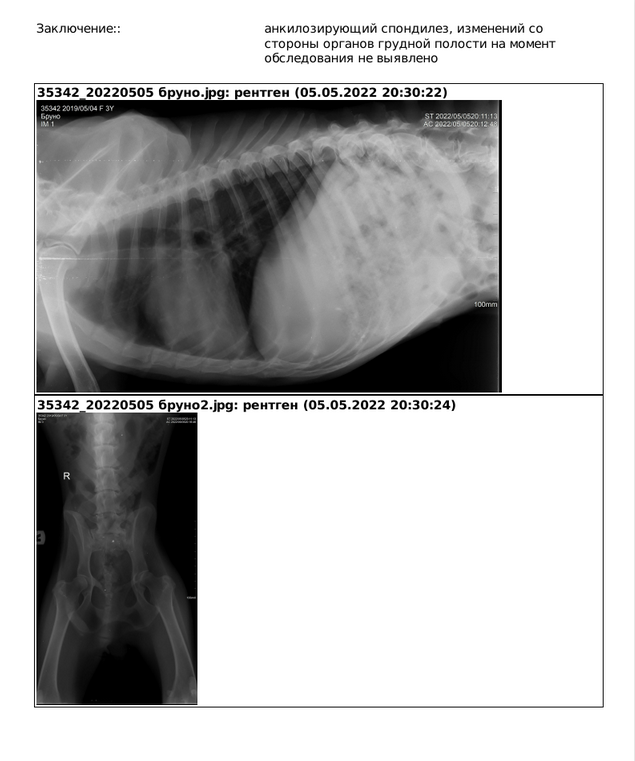

Получили сегодня результат анализов крови, рентген, УЗИ.

Девчулечка Брунечка обязательно поправится! У ребёнка сильное обезвоживание, сегодня весь день были капельницы, только вечером дали жидкую консерву. Аппетит отменный, в перерыве между капельниц - Бруняша проявляла активность, бодрствовала и явно была в хорошем настроении. Температуры нет. В туалет по большому сегодня не ходила, хотя вчера был жуткий понос. По словам доктора девочке около 3 лет. И она по возрасту шило-попа. Сегодня взяты анализы по большому респираторному профилю (готовность ожидаем к субботе). Завтра запланировано обширное обследование по гастропрофилю - будет выполнено УЗИ и даже назначен рентген брюшка. Есть данные за проблемы с кишечником.

Есть все основания полагать, что пироплазмоз мы поймали в самом начале заболевания. Экспрессом посмотрели ОАК - низкий гемоглобин 103 и снижены тромбоциты - 71, остальные показатели в норме. Завтра будут результаты анализов (БХ и ОАК) из лаборатории. Ещё завтра осмотр дерматолога и мазок на демодекоз.